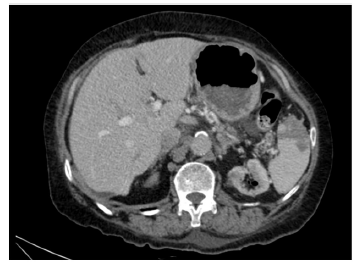

Paciente femenina, de 70 años de edad, con antecedente de infección por el virus de la hepatitis B, cirrosis hepática, hipertensión, hipotiroidismo y extabaquista, con enfermedad renal crónica en estadio 5, terapia de reemplazo renal con diálisis peritoneal, y adicionalmente falla cardíaca con función sistólica preservada. Había consultado previamente por dolor lumbar intenso, discapacitante, en cuyo estudio habían solicitado de manera ambulatoria radiografía de columna lumbosacra para cuya preparación recibió laxante osmótico con posterior cuadro de deshidratación secundario a enfermedad diarréica aguda de alto gasto, con intolerancia a la vía oral, razón por la cual consultó al servicio de urgencias. Presentó episodio de hipotensión y lipotimia, y durante su recuperación refirió disminución de la fuerza muscular en las extremidades inferiores documentando paraplejia arrefléxica en el examen físico. Inicialmente se sospechó compresión medular neoplásica o por hernia discal. Se realizó resonancia magnética nuclear contrastada de columna lumbar que demostró mielopatía, posiblemente isquémica, que comprometía la cauda equina, hemangioma en T7-T8 y abombamiento discal L3-L4 sin compromiso del canal medular (figs. 1-3). Se solicitó angiotomografía de abdomen que evidenció trombo intramural e intraluminal de la aorta abdominal con una extensión longitudinal de 7,5 cm por encima de los vasos viscerales sin disección de aorta, ateromatosis aórtica severa y aspecto irregular, posiblemente ulcerado de la misma, a nivel torácico sospechoso de aorta shaggy (fig. 4), con múltiples infartos esplénicos por tomografía (fig. 5). Ante el cuadro neurológico se sospechó ateroembolia de la arteria de Adamkiewicz; sin embargo, no fue posible visualizarla en las imágenes obtenidas (caso llevado a staff de Radiología y Neurocirugía). Se inició manejo con antiagregación dual, sin anticoagulación, con estatinas de alta potencia. Presentó dolor torácico en reposo, por lo que se realizó ecocardiografía de estrés con dobutamina que fue máxima positiva para isquemia en la pared inferior. Fue llevada a coronariografía y se documentó además enfermedad coronaria de dos vasos con oclusión total de la arteria coronaria derecha y lesión en la arteria circunfleja no susceptible de intervencionismo percutáneo. Por múltiples comorbilidades, edad avanzada y pobre red de apoyo familiar se continuó manejo conservador con antiagregación con ácido acetil salicílico, anticoagulación con warfarina y estatinas de alta potencia.

Figura 4 Tomografía de abdomen que muestra trombo intramural e intraluminal al interior de la aorta abdominal en aorta de la unión toracoabdominal, por encima de vasos viscerales, en una extensión longitudinal de 7,5 cm. Se extiende hasta el origen del tronco celíaco sin comprometerlo y se asocia a flap con disección focal.